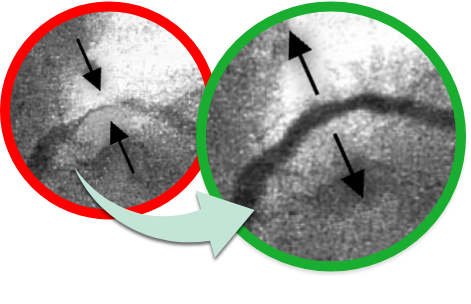

Fotografie vlevo, pořízená během koronární angiografie, ukazuje výrazné zúžení krevních cév ucpaných usazeninami cholesterolu. Na fotografii vpravo: krevní cévy po použití kardioaktivní formule - usazeniny cholesterolu byly natrvalo odstraněny a lumen cév byl výrazně rozšířen. Krev může volně cirkulovat, netvoří se embolie a sraženiny.